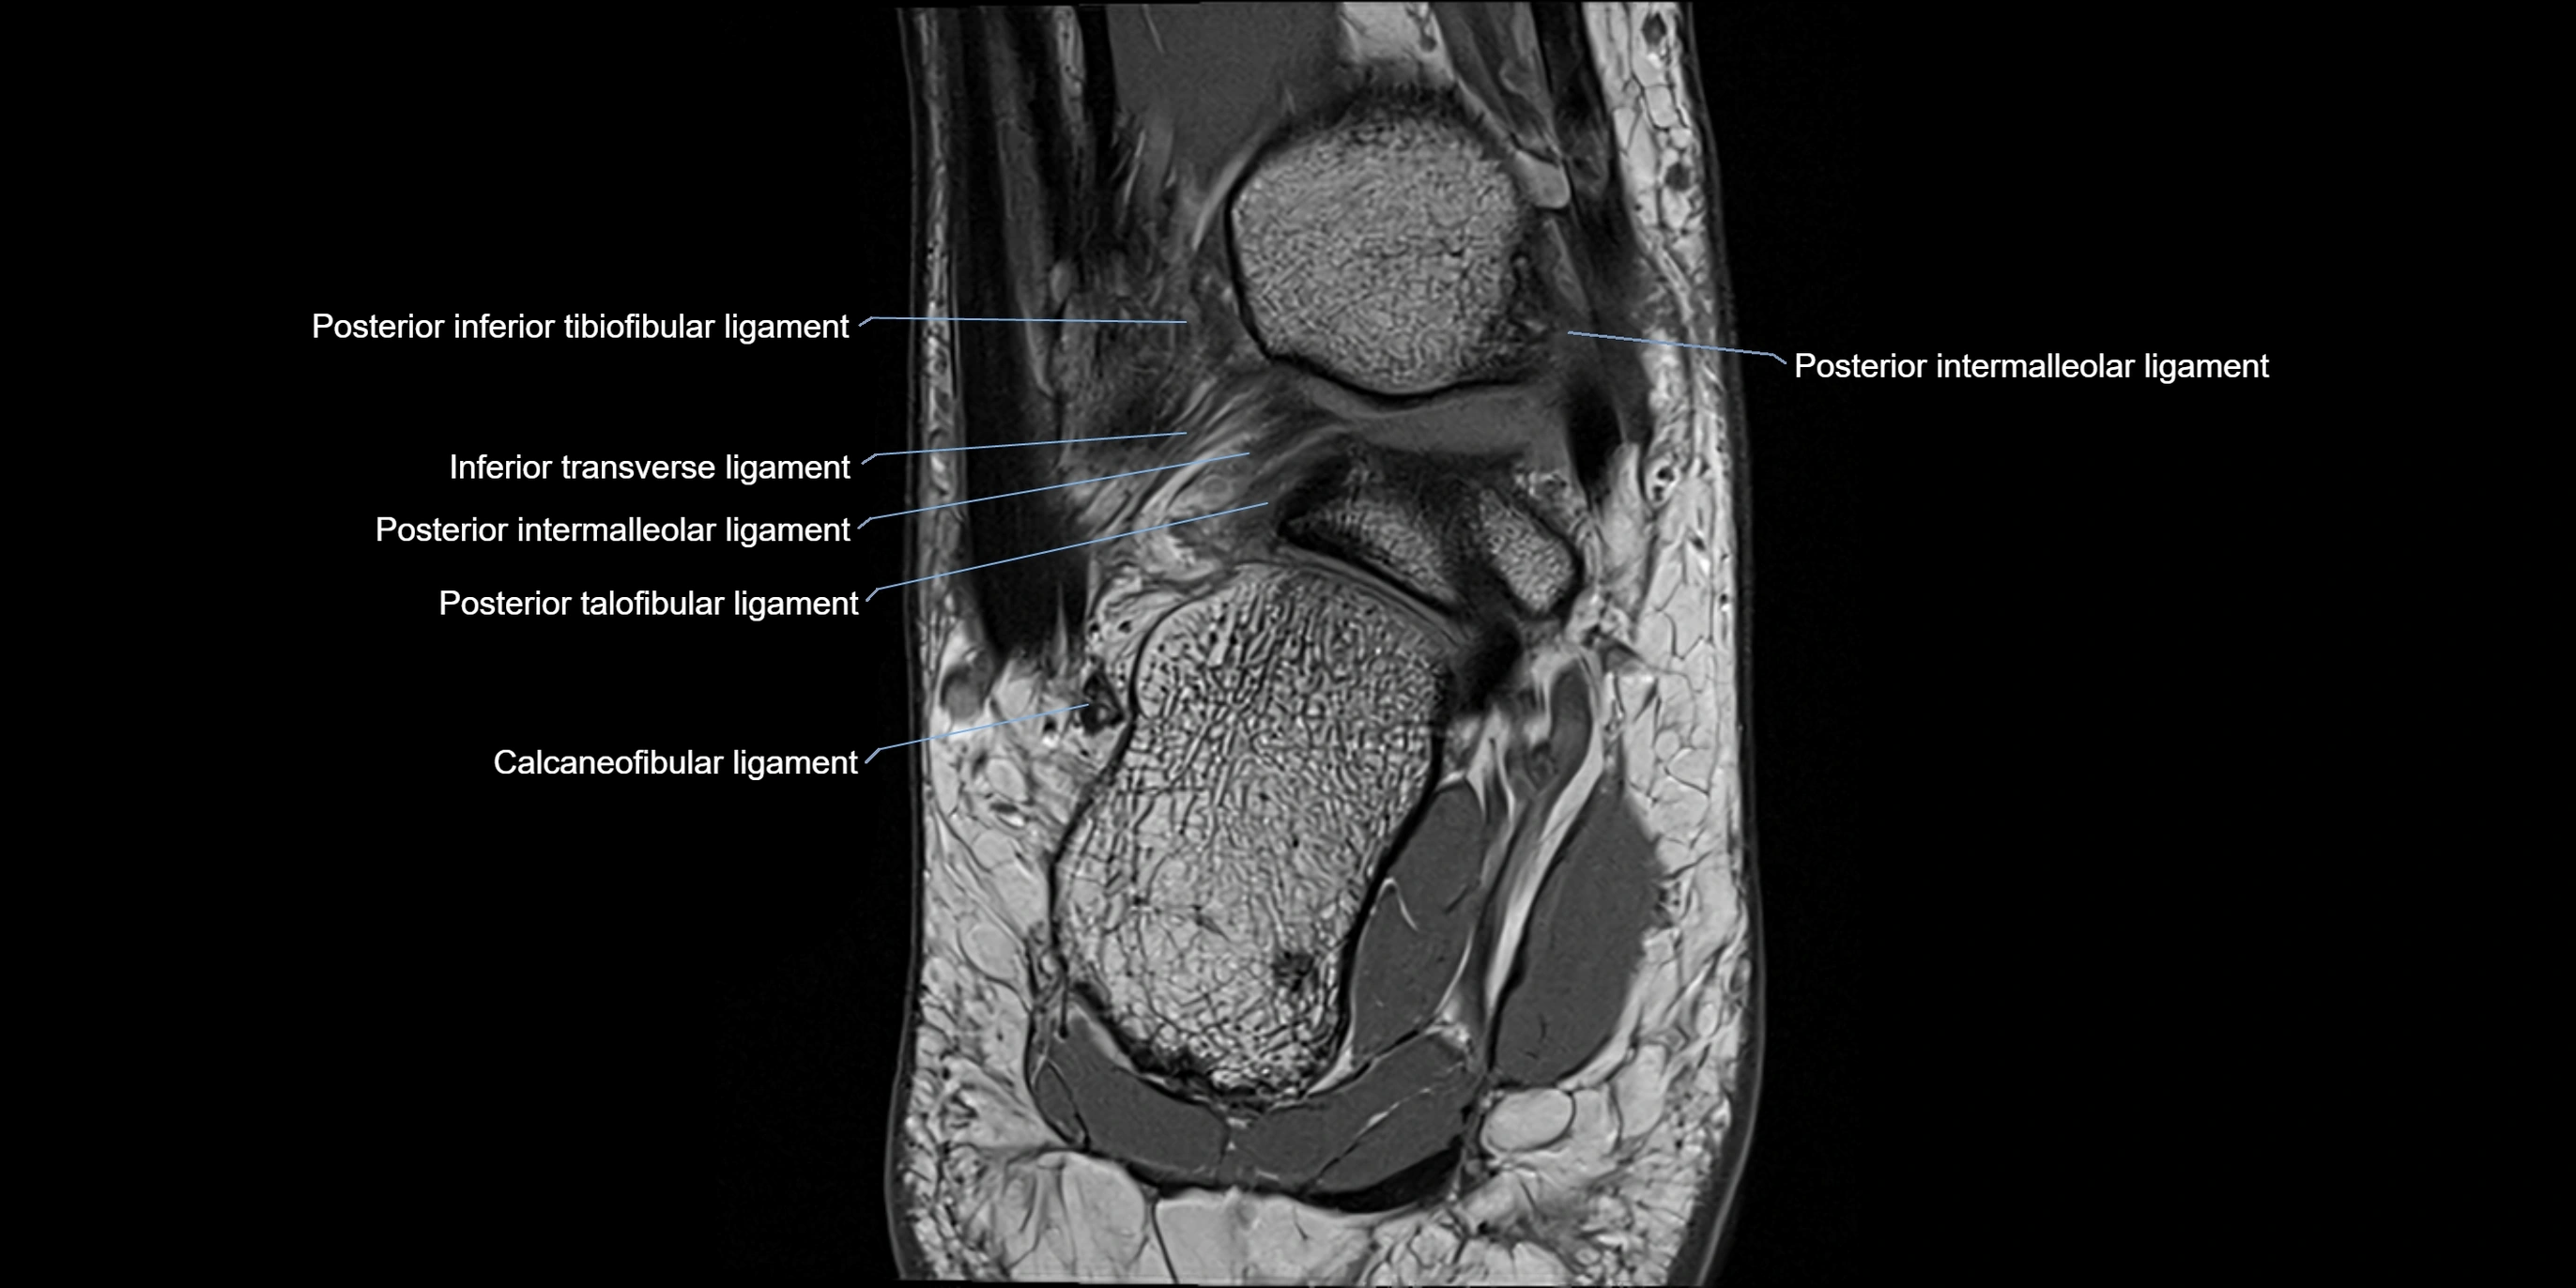

MRI image

image